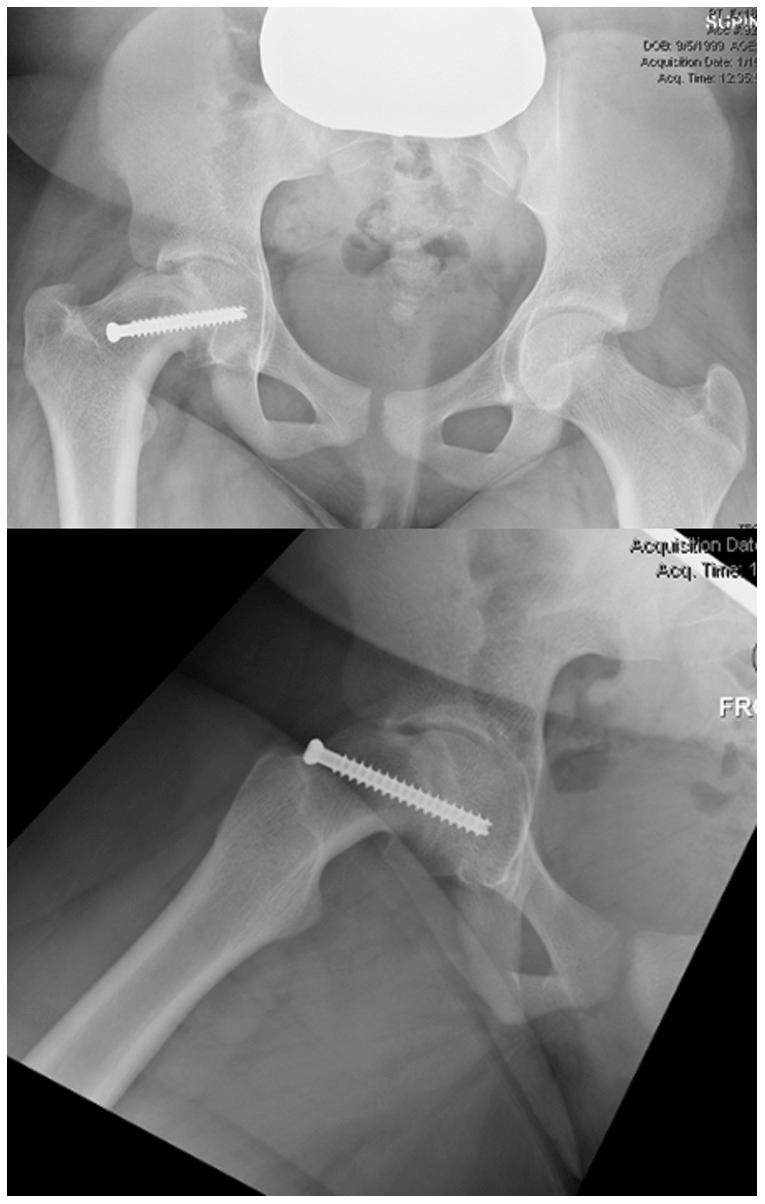

An evolution in conceptual understanding, coupled with technical innovations, has enabled hip preservation surgeons to address complex pathomorphologies about the hip joint to reduce pain, optimize function, and potentially increase the longevity of the native hip joint. Technical aspects of hip preservation surgeries are diverse and range from isolated arthroscopic or open procedures to hybrid procedures that combine the advantages of arthroscopy with open surgical dislocation, pelvic and/or proximal femoral osteotomy, and biologic treatments for cartilage restoration.

概念理解的演变与技术创新相结合,使髋关节保留外科医生能够处理髋关节的复杂病理形态,以减轻疼痛、优化功能,并有可能延长天然髋关节的使用寿命。髋关节保留手术的技术方面多种多样,从单纯的关节镜手术或开放手术到结合关节镜优势与开放手术脱位、骨盆和/或股骨近端截骨以及软骨修复生物治疗的混合手术。